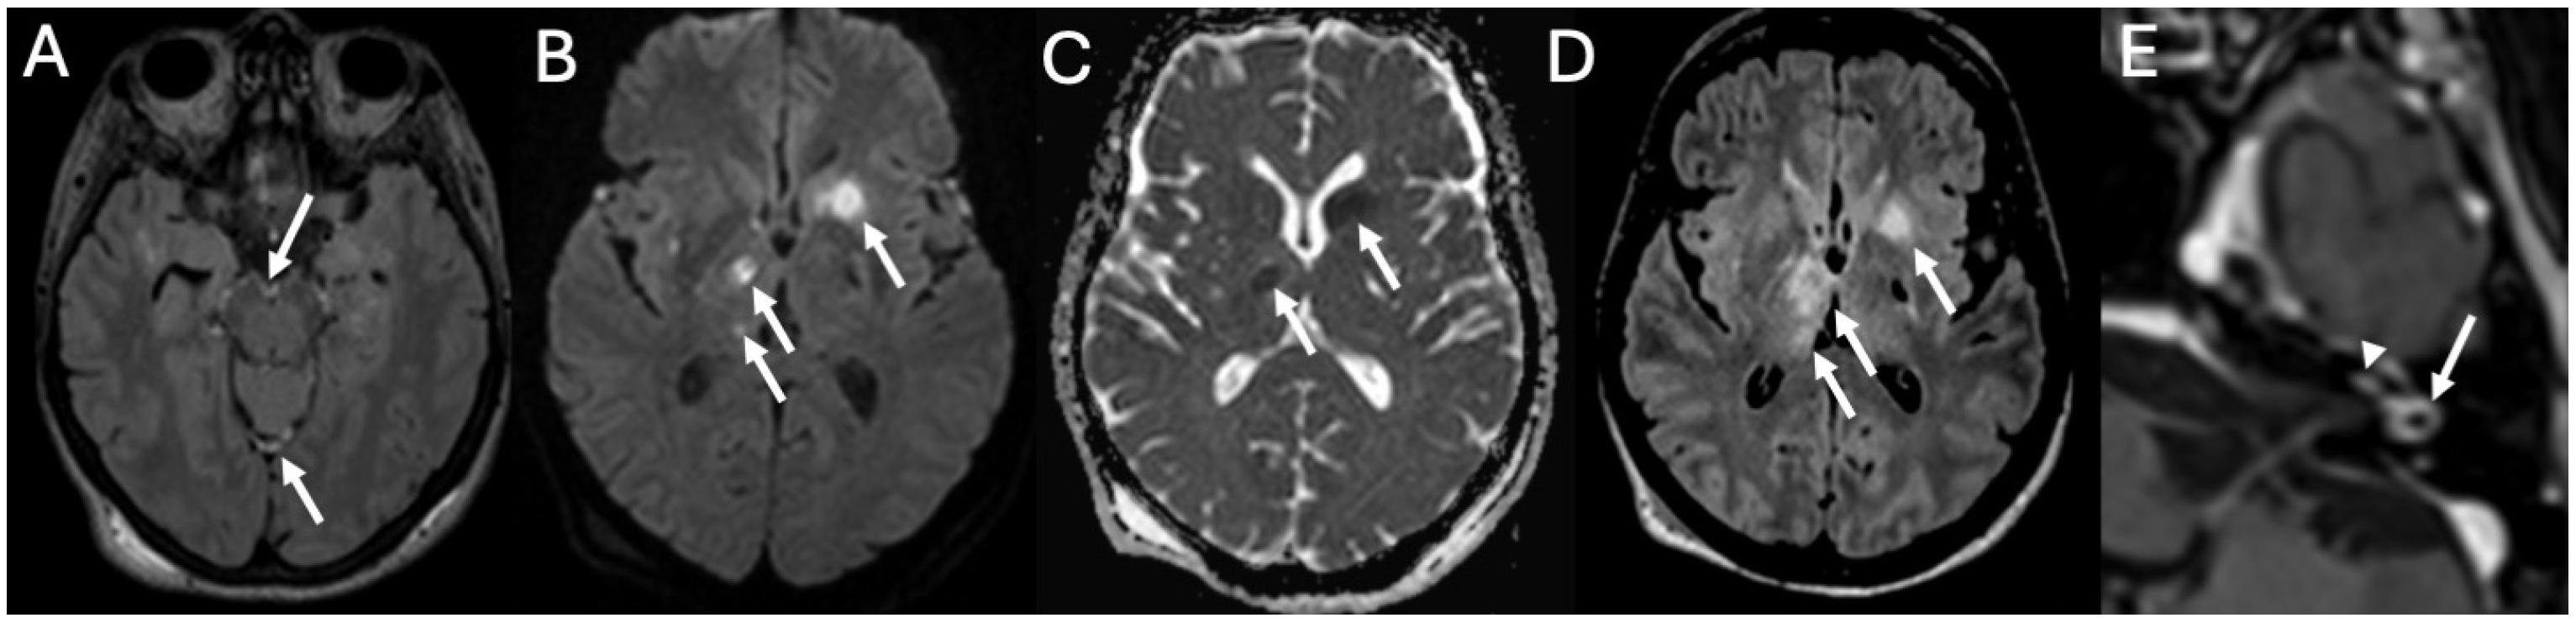

3.5. Cochlear Hemorrhage

| Cochlear Hemorrhage (Rare Complication) | Perillo et al., 2024 [36]; Engelen-Lee et al., 2016 [37] | Case report; pathologic correlation study | First documented case of cochlear hemorrhage secondary to pneumococcal meningitis; likely due to microvascular injury. |